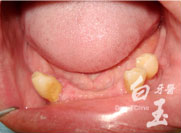

治療過程

治療前

植入植體